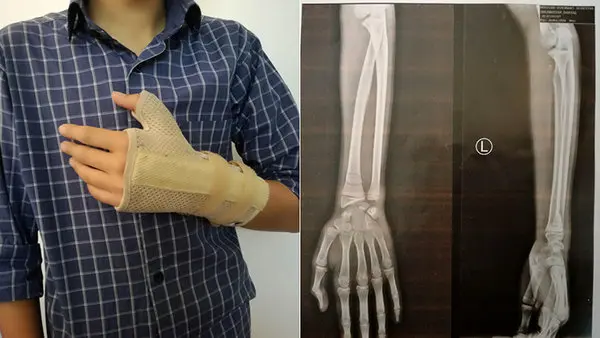

حوادث رکنا: دست پسرم در اثر ضربات معلمش درد زیادی داشت و ما اول فکر کردیم شاید دچار کوفتگی شده و چیز مهمی نیست. ولی وقتی به درمانگاه مراجعه کردیم، متوجه شدیم که دست پسرم شکسته و آن را گچ گرفتیم.

«علی اکبر.ق» میافزاید: دست پسرم در اثر ضربات معلمش درد داشت و ما اول فکر می کردیم شاید دچار کوفتگی شده و چیز مهمی نیست. وقتی روز بعد به درمانگاه مراجعه کردیم، متوجه شدیم که دست پسرم شکسته و آن را گچ گرفتیم.